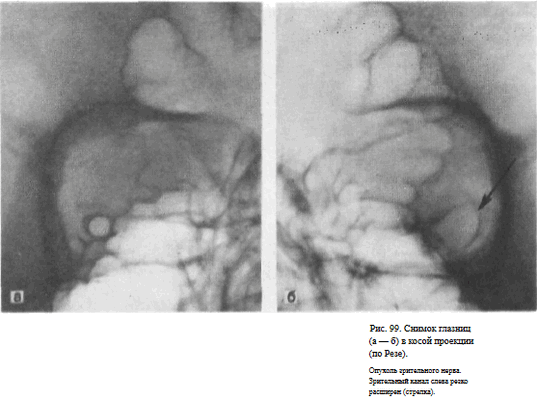

СНИМОК ГЛАЗНИЦЫ В КОСОЙ ПЕРЕДНЕЙ ПРОЕКЦИИ (СНИМОК ЗРИТЕЛЬНОГО КАНАЛА ПО РЕЗЕ)

Назначение снимка. Основное назначение снимка — получение изображения зрительного канала, Как правило, для оценки ширины и формы канала прибегают к последовательной съемке правой и левой глазницы.

Пучок излучения направляют отвесно на наружный угол глаза исследуемой стороны (рис. 97).

Информативность снимка. На снимке отображается зрительный канал, имеющий обычно неправильно-округлую форму с четкими резкими контурами. Видны также вход в глазницу, решетчатые ячейки (рис. 98, а, б). Расширение зрительного канала, возникающее при опухолях зрительного нерва, как правило, может быть достоверно выявлено только путем сравнительного анализа снимков правой и левой глазницы (рис. 99, а, б). Поэтому снимки глазниц в косой проекции по Резе всегда следует производить с обеих сторон.

Критерии правильности технических условий съемки и правильности укладки. На снимке должна быть четко видна структура костей.

Изображение зрительного канала при правильной укладке проецируется вблизи наружной стенки глазницы в виде четкой кольцевидной тени.

Наиболее частые ошибки при выполнении снимка. При неправильном угле наклона головы и неправильной центрации пучка излучения отображение зрительного канала нечеткое. При грубом нарушении правил укладки зрительный канал на снимке неразличим.